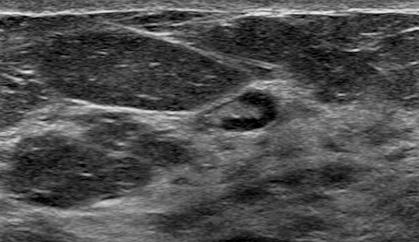

The target dataset was developed from 35 breast ultrasound scans that were segmented by an image-processing expert with extensive experience in breast lesion segmentation (the second author). The images, collected from the Web, are of different dimensions, ranging from to pixels (Figure 3, images resized for sake of illustration). These are the same images used to introduce EFIS originally [1].

Ultrasound images are generally difficult to segment, primarily due to the presence of speckle noise and low level of local contrast. It should be noted that the segmentation of ultrasound actually does require a complete processing chain, (including proper preprocessing and post-processing steps). However, the purpose of using these images was solely to demonstrate that the accuracy of the segmentation can be increased with the application of SC-EFIS.